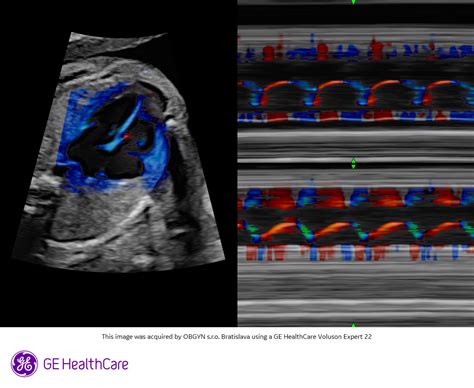

Okrem týchto vyšetrení je tiež možné absolvovať doplnkové diagnostické vyšetrenia, ktoré sú realizované v špecializovaných ambulanciách na liečbu sterility. Do špecializovaných ambulancií sú pacientky častokrát posielané s cieľom diagnostiky priechodnosti vajíčkovodov. Štandardom bola röntgenová hysterosalpingografia, avšak v súčasnosti sa uprednostňuje metóda HyCoSy. Ide o kontrastnú transvaginálnu ultrazvukovú techniku, pri ktorej sa využíva kontrastný gél alebo pena. Prechod tohto gélu vajíčkovodmi je pozorovaný pod ultrazvukom a následne vyhodnotený. Výhodou tejto metódy je, že pacientka nemusí podstúpiť žiadnu hospitalizáciu a ani nie je vystavená röntgeno-ionizačnému žiareniu.